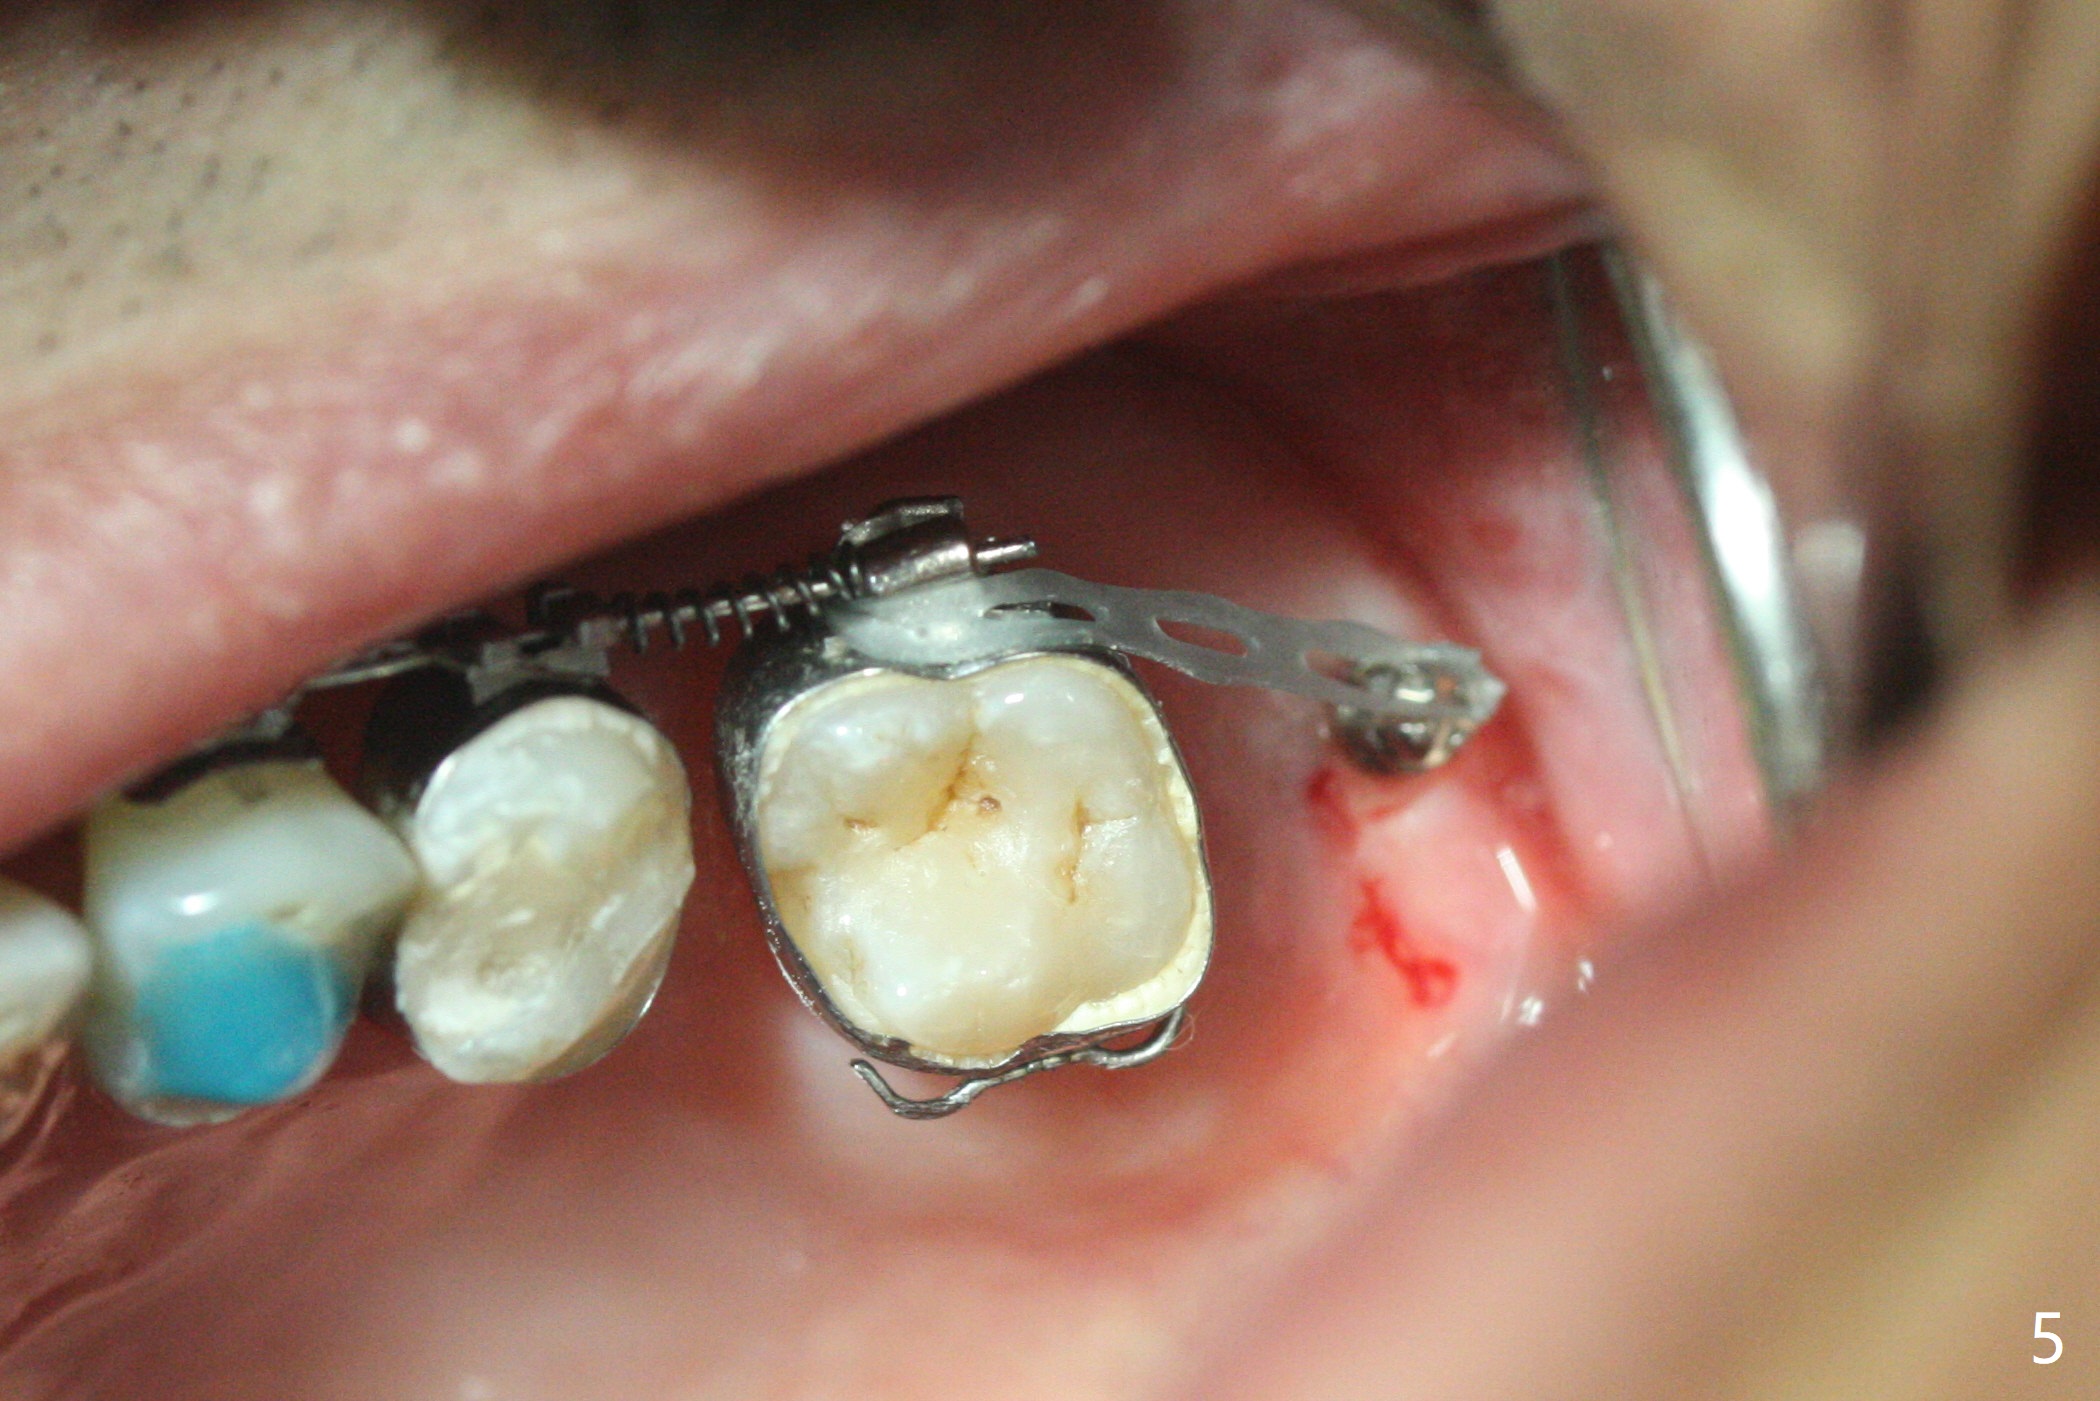

为了在左上6,左下7种植,使用右上3至左上5作为支抗推左上7远中,但是六个月效果不显著(图一),CT显示阻生牙(图一,二:8)没有阻挡。7远中植入1.6x8毫米微型植体,不过接近7根尖(图三),微型植体应该改变角度,而且往远中颊侧移位。最后效果不错(图四),植体马上启用(图五),而且同时取模做左下7导板。在微型植体牵引下,左上7的确往远中移位(图六,与图四对比),但是植体松动,马上植入3x10(2)毫米一段式植体,由于8阻挡,后者没有完全就位,稳定性差,没有启动。几天后也脱落。病人急着完成治疗,因为咀嚼困难。补救方法便是拔除阻生牙9(图七:x),让植体完全就位。切开后发现牙槽嵴处严重骨质吸收缺损(图八:D),离7很近,不适合种植。拔除8后(图九:S(socket)),两处植骨(粘性,图十),覆盖PRF膜,缝合。矫正九个月6空间相当双尖牙(图十二),还想增加2毫米才种植,病人急于完成治疗,所以再次植入微型植体,不同之处是切开,发现7远中颊侧骨质密度低(用探针),因此微型植体在腭侧植入(图十一:P),扭力似乎高,1.6x8毫米植体仿佛植入8牙槽窝(图十二:红虚线)。微型植体牵引一个月,磨牙缺牙间隙大约前磨牙大小,准备在远中(图十三)植入直径小植体(图十四),当后者整合时,用它继续推7。